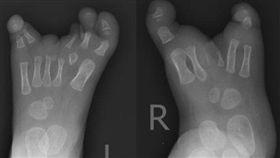

女嬰天生「龍蝦爪」 夢想穿鞋那一天

廣東深圳一名11個月大的女嬰,因為出生就患有先天性裂...